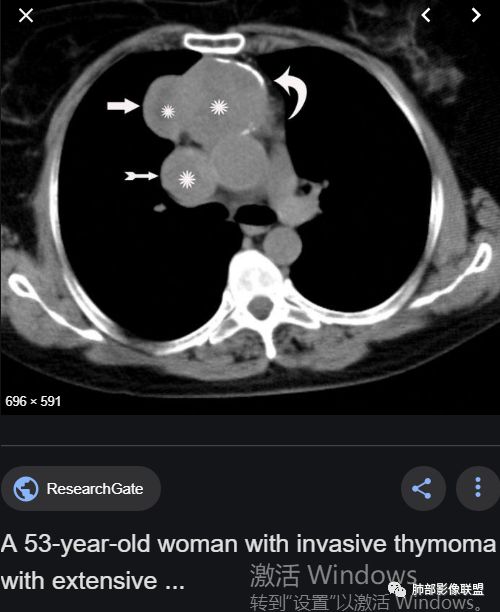

胸腺瘤钙化

大部分钙化还是包膜钙化和条状,结节状钙化,团块状钙化也比较少。位置中央,周围都可以。